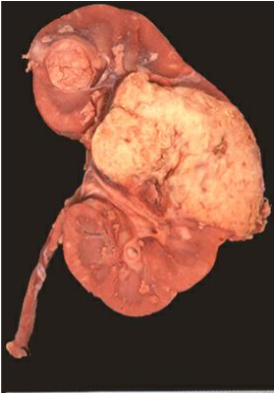

Renal Cell Carcinoma

Top risk factor: Tobacco

Clear Cell (Conventional) type: most common, VHL mutations

Yellow color due to lipids in the clear cells; marked vascularity with hemorrhages (↑VEGF); multiple foci of cystic necrosis

Clear cytoplasm due to Glycogen & Lipids

Early metastasis and renal vein invasion